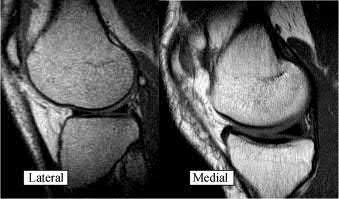

A 27-year-old male is involved in a motor vehicle collision and presents to the ER with the right lower extremity injury shown in Figures A and B. He undergoes immediate closed reduction and the post-reduction CT is shown in Figures C and D. The patient undergoes percutaneous surgical screw fixation of the injury. At 2 years followup, he presents with a supination deformity with decreased eversion of the foot at rest. Radiographs reveal no evidence of talus subchondral sclerosis or collapse. Which of the following is the most likely cause of the finding in this patient?

The patient has sustained a displaced talar neck fracture with medial comminution which requires open reduction and internal fixation to restore anatomic alignment. The patient has likely sustained varus malunion which is a common deformity noted with non-anatomical reduction leading to hindfoot supination and decreased eversion.

Talar neck fractures, while uncommon, can lead to significant morbidity in the ambulatory patient. Treatment of these injuries requires prompt reduction due to the tenuous blood supply to the talus. The most common complications noted after a talar neck fracture are avascular necrosis, subtalar arthritis, tibiotalar arthritis, and varus malunion. A talus varus malunion generally occurs due to medial talar neck comminution and/or non-anatomic reduction of the injury. This deformity can lead to decreased eversion and a supination deformity causing patients to ambulate on the lateral aspect of the foot. These malunions are generally treated with a medial opening wedge osteotomy.

Figures A and B are the Lateral and AP radiographs of a displaced talar neck fracture with tibiotalar dislocation. Figures C and D are the post-reduction sagittal foot CT cuts that reveal a displaced talar neck fracture with medial

comminution.